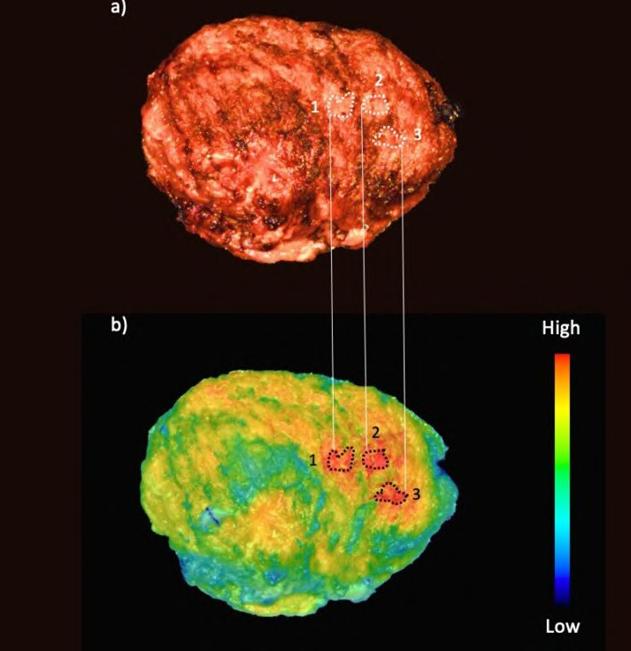

Ultrasound Imaging Tracks Tumor Response to Radiation and Immunotherapy

Image: Ultrasound detection of vascular changes post-RT corresponds to shifts in the immune microenvironment (Photo courtesy of Theranostics, DOI:10.7150/thno.97759)

An interdisciplinary research team from Vanderbilt University (Nashville, TN, USA; www.vanderbilt.edu) has developed an innovative method using ultrafast power Doppler ultrasound to monitor tumor vasculature in real-time in two breast cancer models—metastatic and non-metastatic. By tracking changes in blood vessel networks, the researchers can now gain unprecedented insights into how tumors respond to radiation therapy.